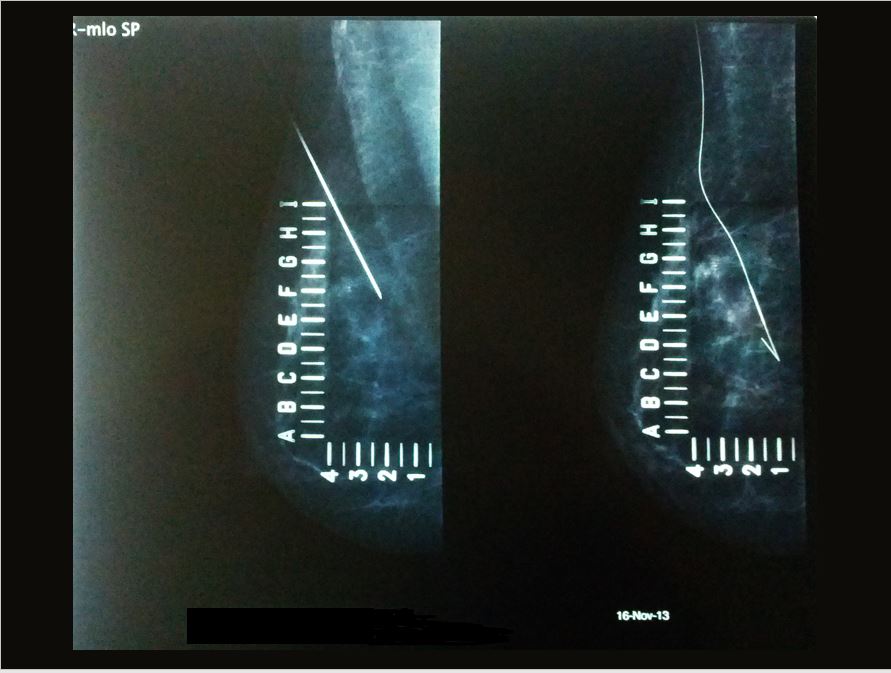

Τοποθέτηση συρμάτινου οδηγού (HOOK)

Σκοπός αυτής της διαδικασίας είναι ο προεγχειρητικός  εντοπισμός μη ψηλαφητών αλλοιώσεων (αποτιτανώσεων, ύποπτων συμπαγών μορφωμάτων) με συρμάτινο άγκιστρο (hook). Η προώθηση του αγκίστρου μπορεί να γίνει με υπερηχογραφική ή μαστογραφική  καθοδήγηση. Η διαδικασία αυτή είναι  ανώδυνη, απλή και σύντομη, χωρίς να χρειάζεται  ειδική προετοιμασία από την εξεταζόμενη.

Η τοποθέτηση του συρμάτινου οδηγού, διευκολύνει τον χειρουργό και οδηγεί στη μείωση του χρόνου της επέμβασης, στη μείωση του όγκου του αφαιρούμενου ιστού, στο καλύτερο αισθητικό αποτέλεσμα και στην καθοδήγηση της ιστολογικής εξέτασης.

∆ιεγχειρητικά το παρασκεύασµα που έχει αφαιρεθεί στέλνεται για ακτινογραφία- μαστογραφία, ώστε να διαπιστωθεί ότι η περιοχή µε τις αποτιτανώσεις έχει αφαιρεθεί πλήρως και κατόπιν το δείγµα στέλνεται για ιστοπαθολογική εξέταση. Επίσης αξιολογείται η απόσταση της αλλοίωσης απο τα όρια του δείγματος, για να κριθεί εάν απαιτείται ευρύτερος χειρουργικός καθαρισμός. Σε αρκετές περιπτώσεις στην περιοχή της εκτοµής τοποθετούνται µεταλλικοί δείκτες (clips), ώστε αν χρειαστεί επιπλέον συμπληρωματικό χειρουργείο ή βιοψία, να είναι εύκολος ο εντοπισµός της προηγηθείσας επέµβασης.

Τοποθέτηση συρμάτινου οδηγού (hook)  υπό μαστογραφική καθοδήγηση.

Αρχείο Δρ. Ειρήνης Αγγελίδου.